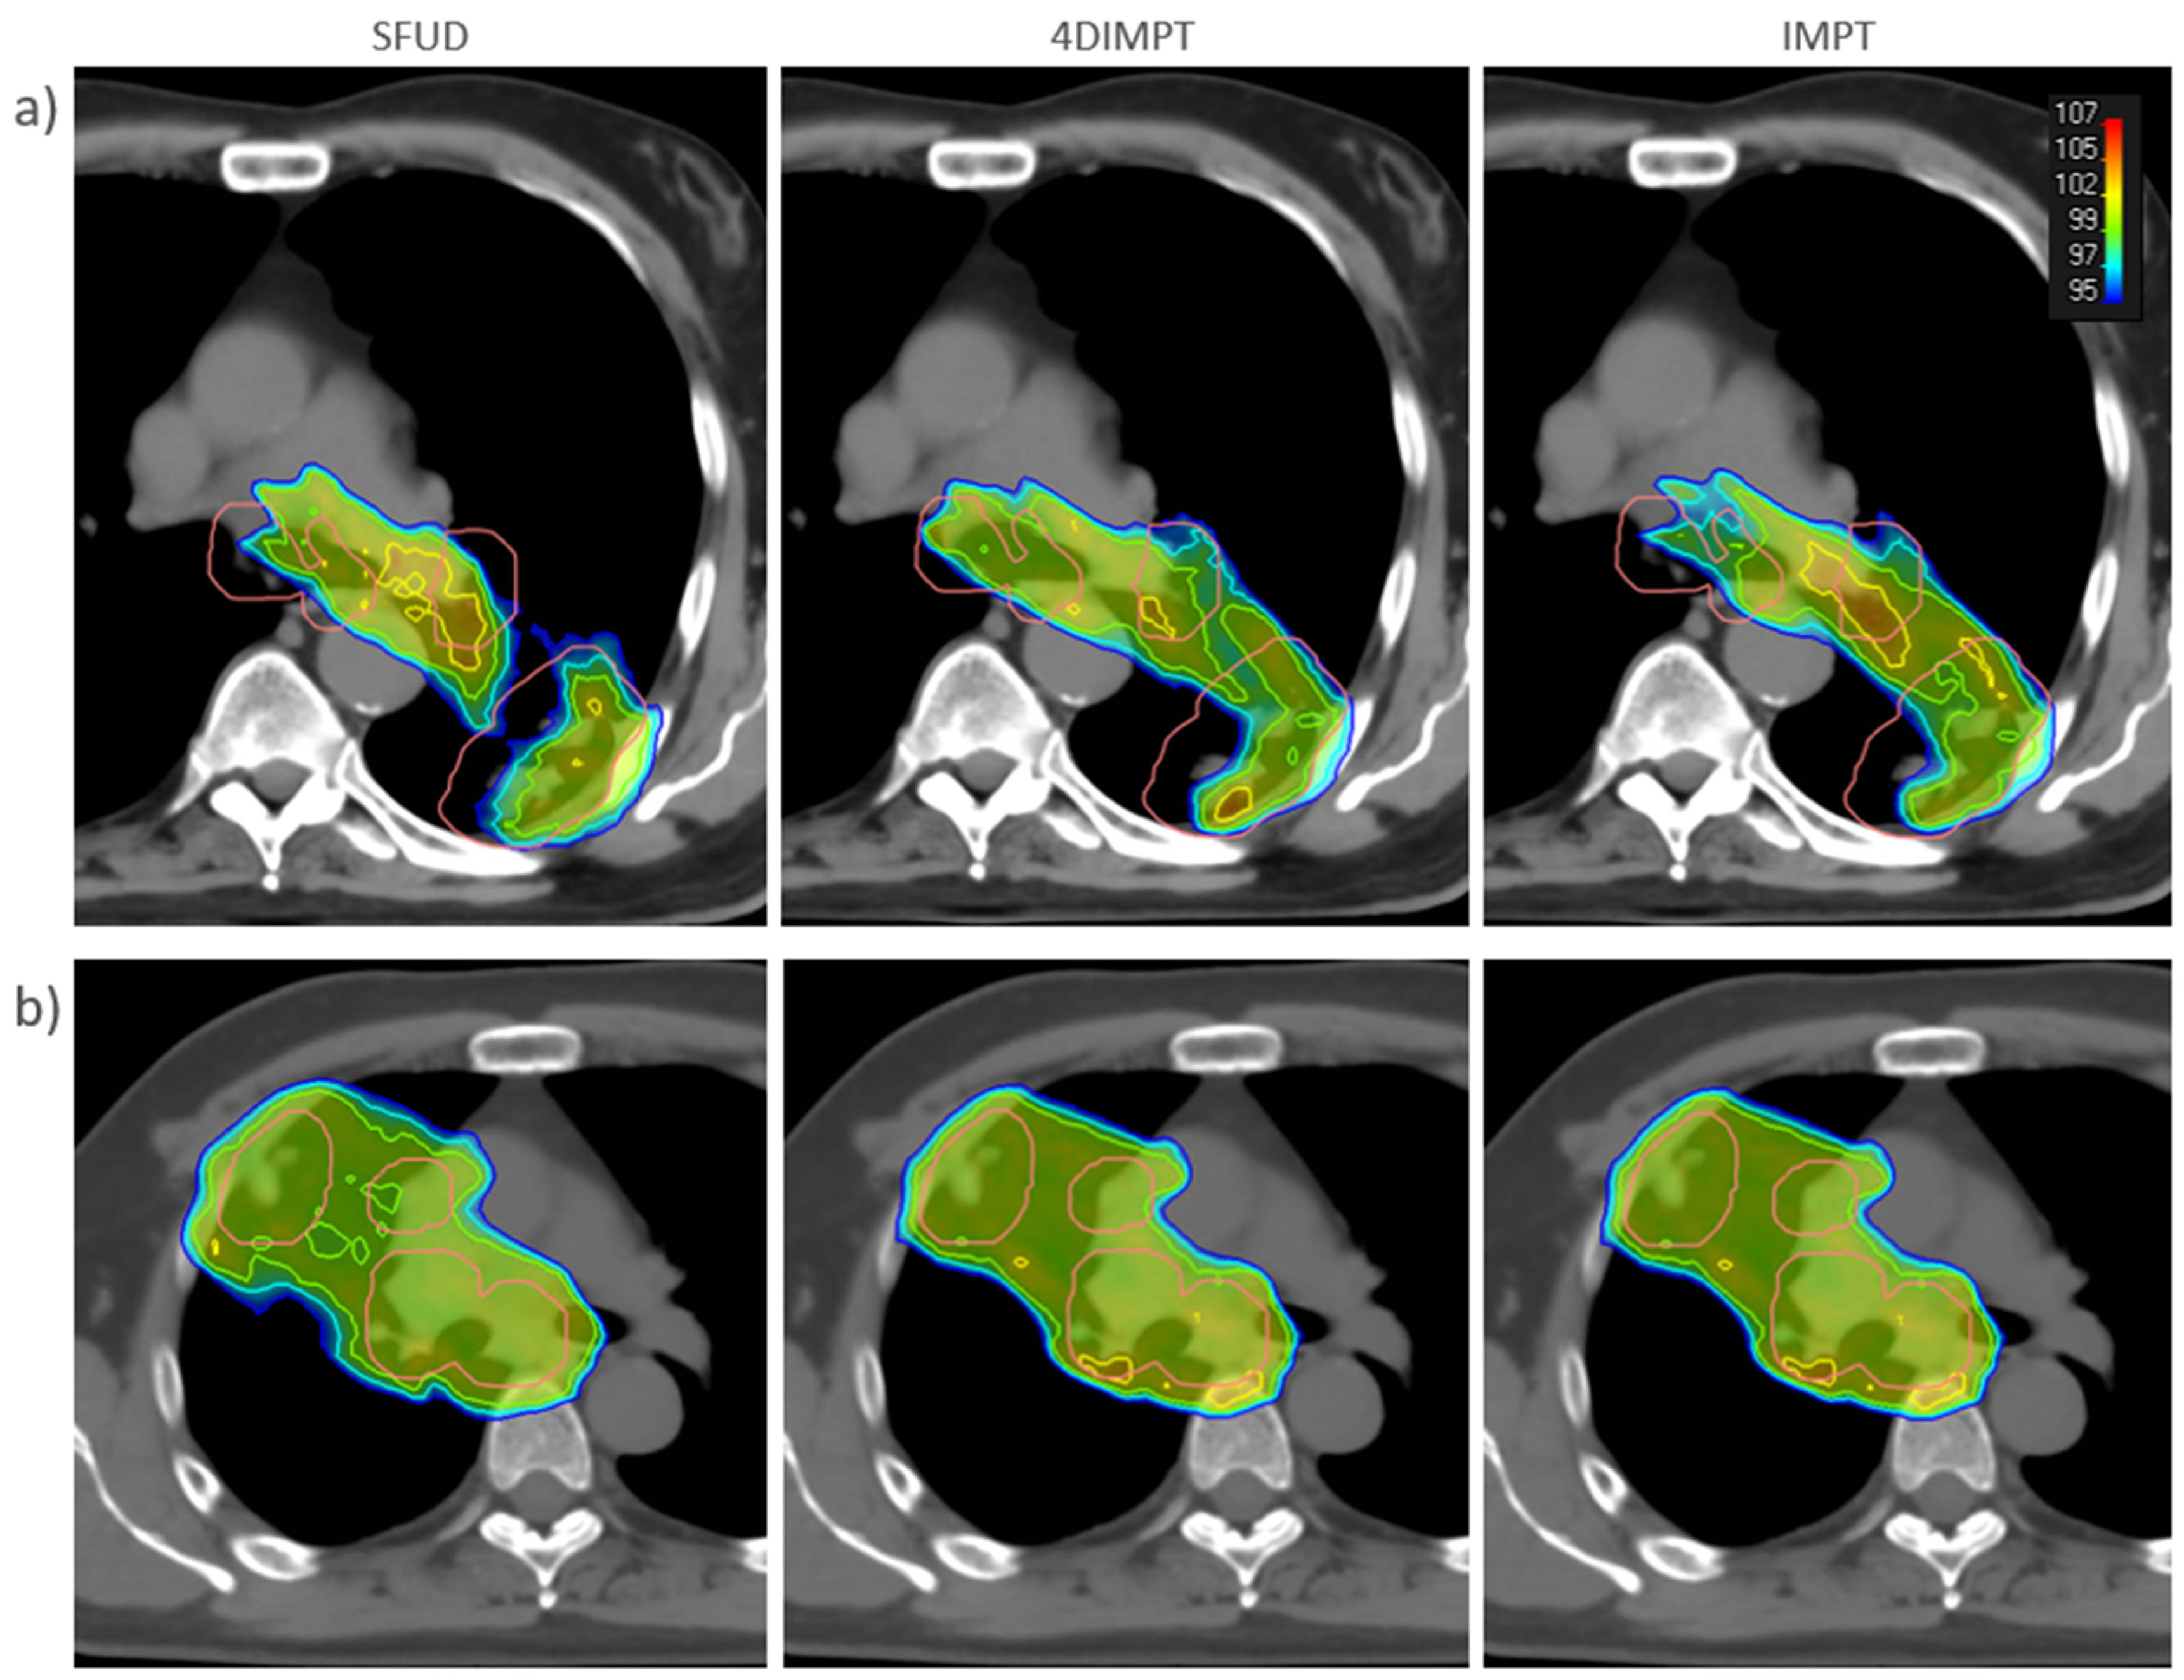

3.2. Target Coverage and OAR Sparing at Plan

3.3. Target Dose Robustness at Plan and Start

3.4. OAR Dose Robustness at Plan and Start